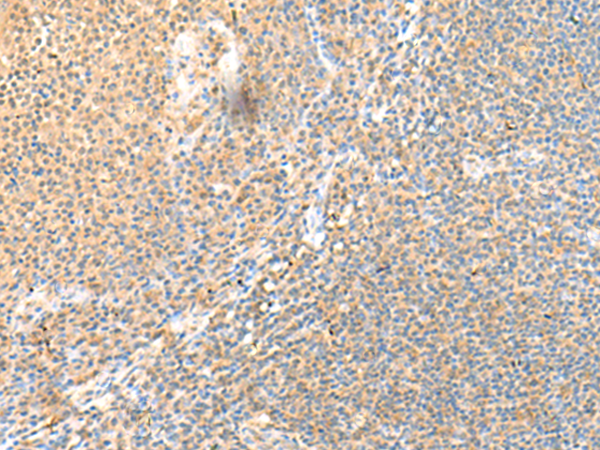

分类: 科研抗体货号: P09849别名: SRCRB4D; S4D-SRCRB; SRCRB-S4D应用: IHC反应种属: Human